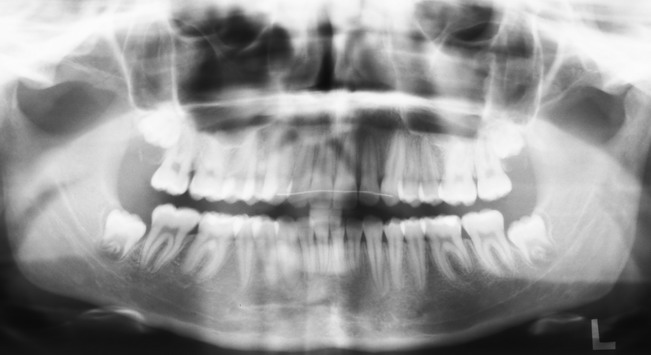

Eine röntgenologische Übersichtsaufnahme der Zähne

Die Übersichtsaufnahme der Zähne – auch „Orthopantomogramm“ oder kurz „OPG“ genannt – ermöglicht eine Beurteilung der Zahnwurzeln und der knöchernen Kiefer. Dank eines OPG werden überzählige oder verlagerte Zähne ebenso erkannt wie verkrümmte oder fehlentwickelte Zahnwurzeln. Auch Nichtanlagen – also das Fehlen bleibender Zähne – werden nur durch das OPG sicher diagnostiziert. Deshalb ist diese für die Behandlungsplanung unerlässlich.